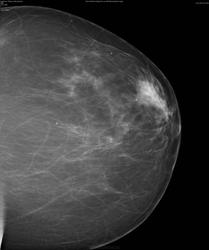

Опухоль находится в субареолярной области слева. К счастью -пальпировалась.Мы выполнили стандартное исследование- результат(Вы видите) не убедительный. Потом пальпаторно выявили подозрительное место и выполнили прицельный снимок.Ориентиром была пальпация. Я представил этот случай к рассуждениям о проведении маммографии только в косых проекциях. В данном случае полноценного исследования(в 2-х стандартных проекциях) оказалось мало.